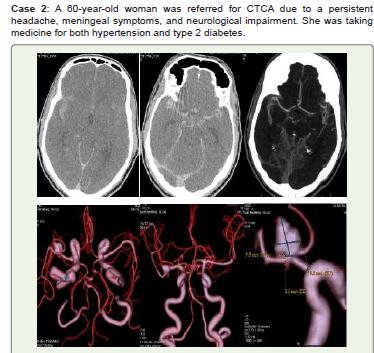

Figure 2:Acute SAH is visible in basal cisterns, sylvian fissures,

interhemispheric fissures, and along the tentorium cerebelli on noncontrast

CT (A, B). A medium multilobed Saccular aneurysm measuring 9.5x6 mm

with a neck diameter of 3.5 mm is shown at the right MCA bifurcation in

CTCA (C) and 3D-VR images (D, E, and F). She had conservative care and

was recommended for endovascular therapy and /or surgical clipping.